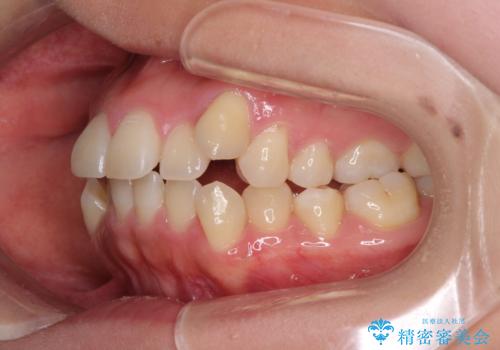

- 八重歯と前歯のデコボコを気にして来院された患者様です。

八重歯の他に、上顎歯列を狭窄しているという問題点がありました。

また、八重歯により上顎奥歯が前方に位置しており、咬み合わせの改善も必要な状況でした。

八重歯の動きが鈍く、治療期間は長期化しました。

癒着の疑いもありましたが、アンカースクリューを多用し、何とか改善することができました。